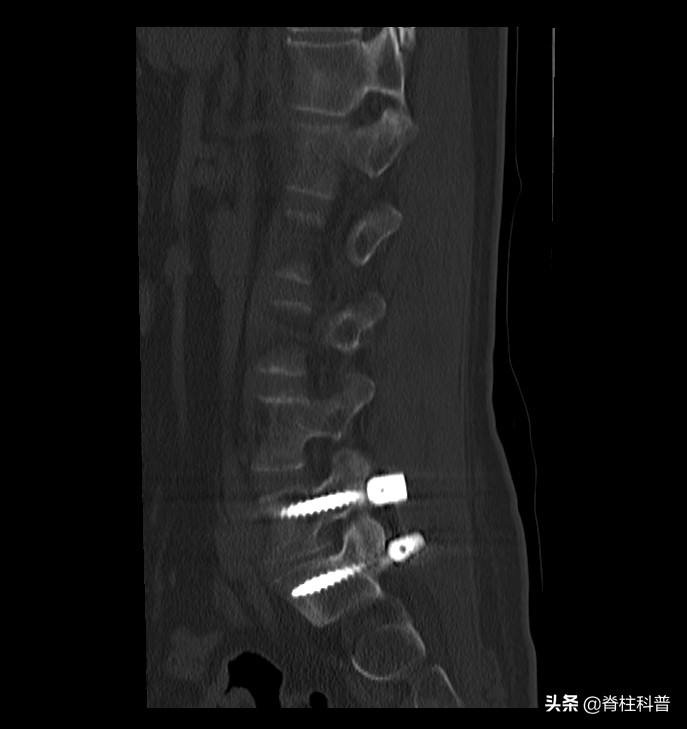

术后CT片子